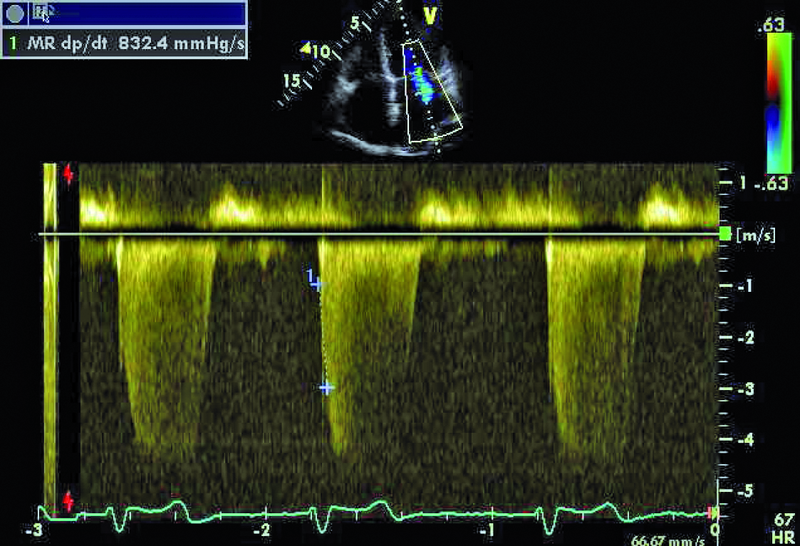

Kobieta, lat 80. Jakie patologie można rozpoznać na rycinach?

7. Niedomykalność zastawki mitralnej (ryc. 6).